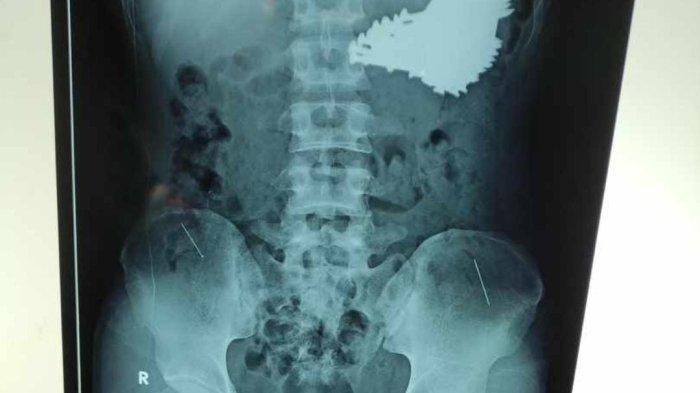

Kondisi SH , pria ODGJ usia 22 tahun ini terkuak dari hasil rontgen yang menunjukkan banyak paku berukuran besar di dalam lambungnya.

Dari hasil rontgen, terdapat puluhan paku yang bersarang di dalam lambung.

Di lambung pria tersebut ditemukan 70 paku.

Kondisi SH pun terkuak dari hasil rontgen yang menunjukkan banyak paku berukuran besar di dalam lambungnya.

Dari dalam perutnya berhasil dikeluarkan 70 paku yang sudah berkarat.

Hasil rontgen tersebut menunjukkan ada banyak paku berukuran besar yang bersarang di dalam lambung.